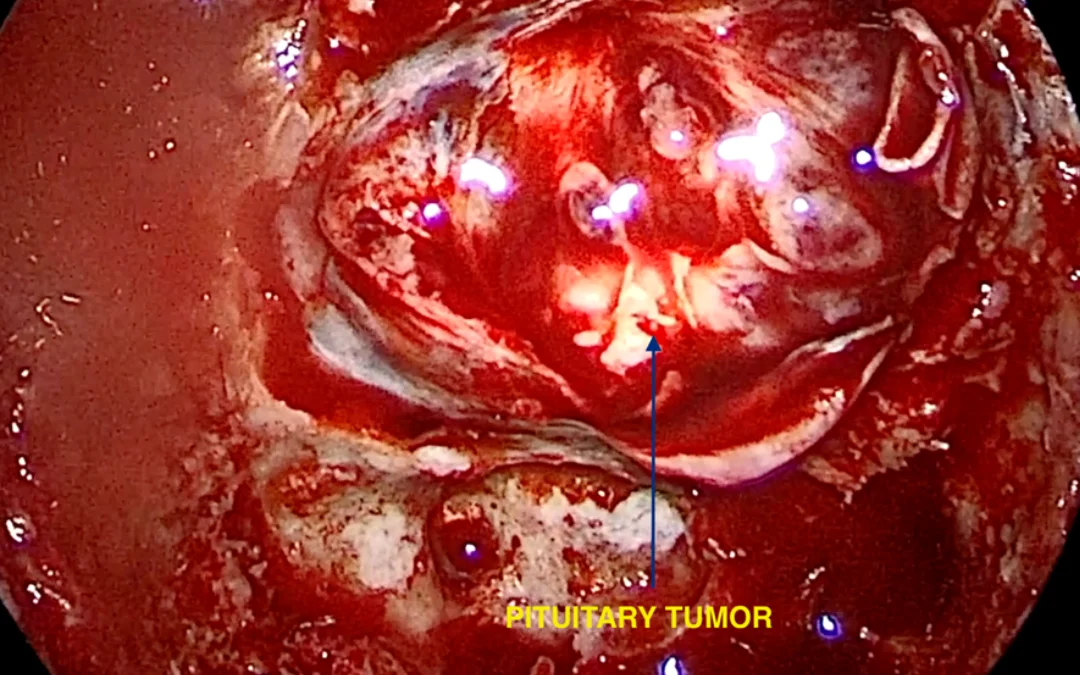

How surgery is performed?

Now a days most of these tumors are generally treated with endoscopic surgery through nose . Really for large tumors craniotomy ( opening of skull) is required.

OPERATIVE VIDEO LINK: DETAIL VIDEO LINK: https://youtu.be/bNISxyotyCU